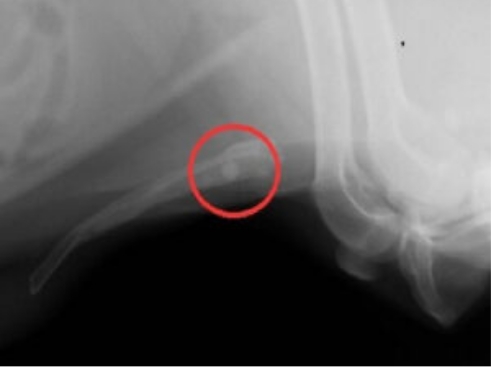

12歳のウエスティー リンちゃん。

雪道を散歩中に突然腰が落ちるようになり『キャン』と鳴いた後から左後肢が着かなくなり来院されました。

• レントゲン写真1

• レントゲン写真2

レントゲンで左後肢の脱臼所見が認められました。麻酔下で非観血的に関節を戻し包帯で固定を行いましたが、数日で再脱臼を起こしてしまいました。飼い主さまと幾つかの治療プランや今後の経過プランを相談し大腿骨頭切除術を行うことにしました。